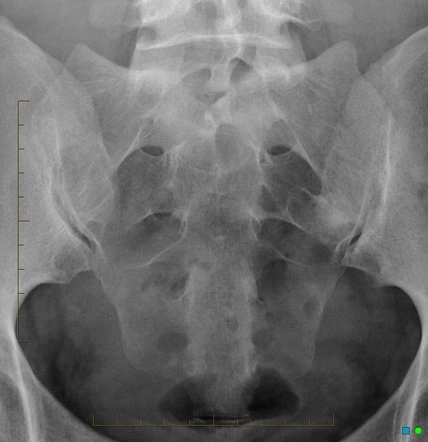

The sacrum lateral view shows the most backward part of the spine from the side. The Sacrum anteroposterior (AP) view shows the Sacrum and how it connects to other bones.

• The sacrum anteroposterior (AP) view can look for damage or see if the sacrum and/or sacroiliac joints have deteriorated.

• The Sacrum (lateral view) Test helps to see what's wrong with the Sacrum and coccyx and looks into the cause of both short-term and long-term pain in those areas. This projection is often used with the AP projection.